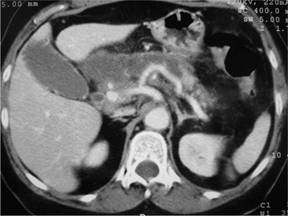

A 65-year-old woman was admitted to our unit with recurrent acute necrotising pancreatitis after several previous admissions to a general county hospital. Past medical history included hypertension, hyperlipidaemia and a raised BMI of 35 kg/m2; there was no history of previous abdominal surgery. She presented with copies of her previous blood results demonstrating a haematocrit of 0.36 (reference range: 0.36-0.44), white blood cell count of 10.3 x109/L (reference range: 3.7-11.0 x109/L), platelet count of 255 x109/L (reference range: 150-450 x109/L), glucose of 118 mg/dL (reference range: 30-61 mg/dL), LDH of 355 IU/L (reference range: 125-243 IU/L), calcium of 9.6 mg/dL (reference range: 8.4-10.5 mg/dL), CRP of 67 mg/L (reference range: 0-5 mg/L), cholesterol of 219 mg/dL (reference range: 120-200 mg/dL), triglycerides of 199 mg/dL (reference range: 70-150 mg/dL) and a CA 19-9 of 261 IU/mL (reference range: 0-40 IU/mL); serum and urine concentrations of amylase were both within the normal range. On this admission her investigations included an ultrasound of the liver and biliary tree, an abdominal CT and a MRI-MRCP. The ultrasound found a thick-walled gallbladder containing sludge and multiple small gallstones in conjunction with dilatation of the common bile duct. The CT (Figure 1) measured the common bile duct dilatation at 7 mm at the level of the head of the pancreas as well as revealing several peripancreatic fluid collections of low attenuation. MRI-MRCP further characterised this and showed oedema of the head of the pancreas with multiple fluid collections but did not demonstrate further distension of the intra- or extra-hepatic biliary tree (Figure 2).

Figure 1. Axial CT image demonstrating bile duct dilatation. |